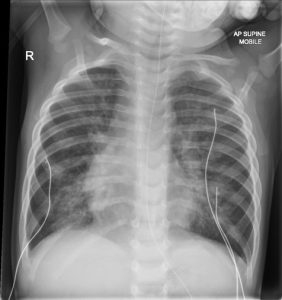

- Pemeriksaan penunjang :

– Rontgen thorax/CT Scan